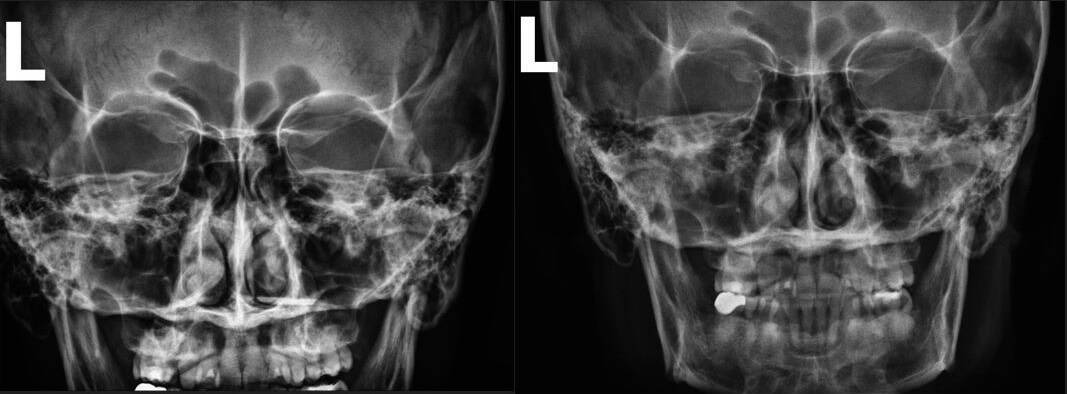

Pre & Post Scan